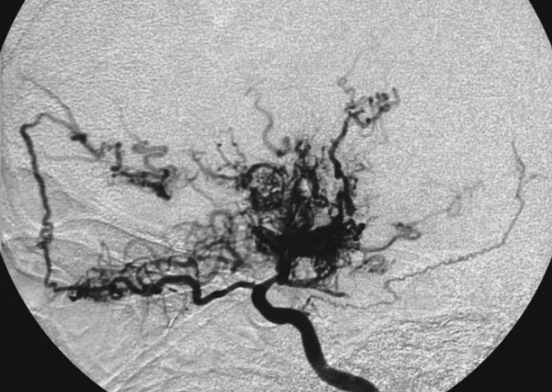

모야모야병은 뇌 혈관이 좁아지는 희귀 질환입니다. 주로 한국과 일본 등 동아시아인들에게 나타나는 희귀 질환으로 우리나라 통계는 없지만 인구 100만병당 1명 정도로 나타나는 것으로 알려져 있습니다. 모야모야는 '연기를 피어오르는 듯한 모양'을 뜻하는 일본말로 뇌혈관 영상검사를 살펴보면 좁아진 혈관이 마치 연기 모양과 비슷해서 붙여진 병명입니다.

모야모야병을 진단하기 위해서는 뇌혈관 영상검사가 필요합니다. MRI, CT 검사 모두 가능하지만 정확한 혈관협착 상태를 확인하기 위해서는 뇌혈관 조영술이 가장 중요합니다. 뇌혈관 조영술 소견에서 양측 내경동맥, 전대뇌동맥, 중대뇌동맥 부위에 협착 혹은 폐색이 있는 경우, 연기 모양의 혈관이 보이는 경우 확실하게 진단이 가능합니다.